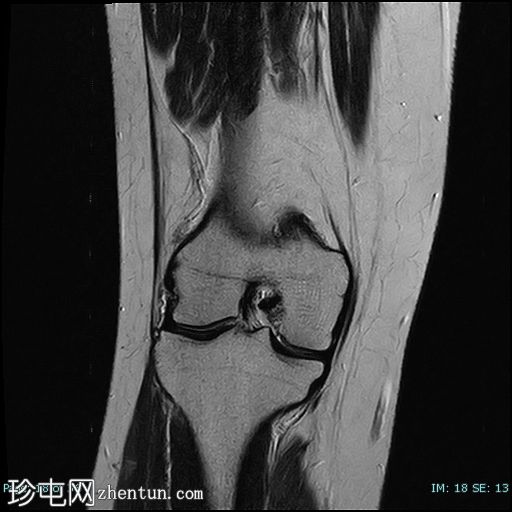

冠状位

T2加权像

8.jpg